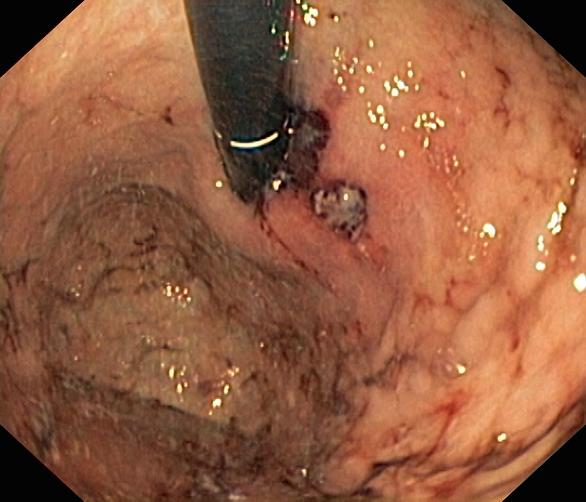

Krwawienie